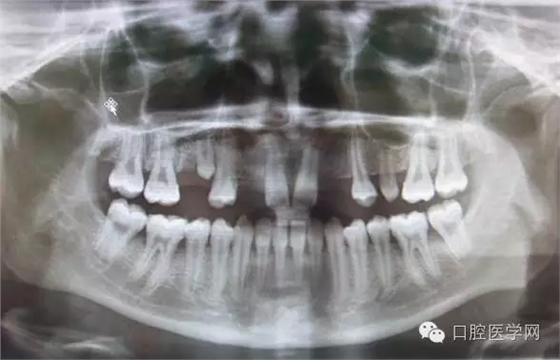

3.牙齒數(shù)目異常

額外牙

X線表現(xiàn):最多見于上頜兩中切牙之間;圓錐形,根短小;拍攝X線片可確定額外牙的數(shù)目、位置、形態(tài)與鄰牙的關(guān)系。

先天缺牙

X線表現(xiàn):常為對(duì)稱性;確定缺牙數(shù)目。